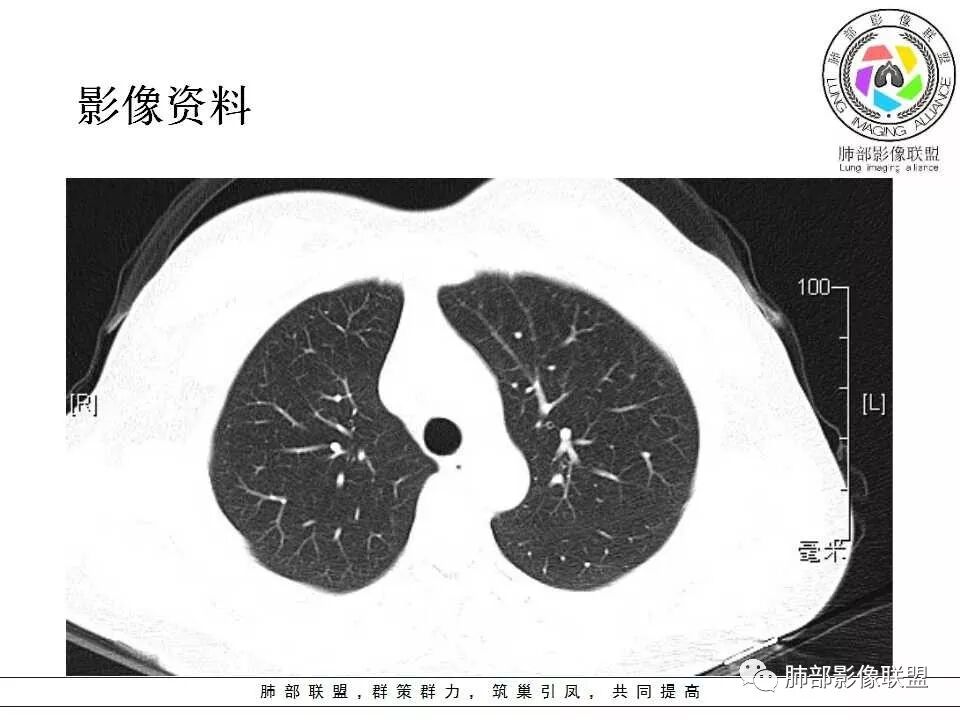

左肺门肿块,边缘光滑清晰,血管贴边,明显均匀强化,考虑PSP,鉴别类癌。

学习一下南大的诊断思路,左肺门区病灶,应该没跨叶,感觉都在上叶,强化密度均匀,边缘清晰,与支气管关系不大,常规考虑良性病变,PSP可能性大,鉴别CD,血管源性。但是一年增大怎么解释,不知道增大多少。

左肺病灶与支气管关系密切,类癌粘膜下生长,支气管略变窄,支气管外病变较大,符合冰山征表现,一年内有增长,考虑类癌,鉴别PSP,建议薄层重建。

我怎么又感觉跨叶间裂了,而且有胸膜尾征和可疑的指状突起,强化很明显,考虑SFT可能大,鉴别类癌和CD

年轻女性,左肺门区肿块,边缘光整,随诊有增大,恶性可能,类癌?鉴别psp、CD。

患者中年女性,发现左肺上叶占位,随访发现体积增大。胸部CT:左肺上叶尖后段实性占位,位于支气管旁,未见支气管阻塞,病灶边界清楚,边缘光滑,增强可见病灶均匀强化,血管贴边,考虑良性病变,PSP?

左肺上叶后段紧贴斜裂结节影,支气管通畅,斜裂无移位,说明病灶来源斜裂可能,强化密度均匀,边缘清晰,考虑良性病变,PSP可能性大,鉴别CD。

青年女性,慢性病程,实验室指标末提及,左肺门区肿块,边缘光滑,无明显分叶,周围清晰,增强明显强化,血管贴边,复查有增大,考虑良性或低度恶性病变,PSP?

患者中年女性,发现左肺上叶占位1年余入院,随访发现体积增大。胸部CT:左肺上叶尖后段近肺门及叶间裂实性类圆形结节,病灶边界清楚光滑,增强可见病灶明显均匀强化,其旁未见支气管堵塞。综合考虑良性病变,孤立性纤维瘤可能,鉴别巨大淋巴结增生症及硬化性肺细胞瘤。

青年女性,左肺门占位,边缘光滑,强化均匀,考虑为良性病变,PSP可能,近期复查增大,不除外恶性病变。

年轻女性,体检发现,左肺上叶近肺门处结节,边缘光滑,均匀明显强化,血管贴边,支气管无关,考虑PSP。

中年女性,发现左肺上叶占位。胸部CT:左肺上叶尖后段孤立卵圆形实性病灶,位于支气管旁,边界清楚,边缘光滑,血管贴边,肺动脉为主征,增强扫描明显均匀强化。考虑:PSP?鉴别CD、类Ca。

青年女性,左肺门占位。定位:跨叶间裂,下叶邻近支气管推压,考虑肺外病变。影像表现:血管贴边,边缘光滑,强化均匀,考虑良性病变,PSP可能大,鉴别CD。

左肺上叶类圆形实性病灶,边缘光滑,可见血管贴边征,病灶与左肺上叶支气管关系密切,左肺动脉相对增粗,增强病灶均匀强化,常规考虑PSP,其次神经内分泌肿瘤不排除。

厚层,只有动脉期。左肺门占位,边界清,动脉期强化比较明显,后段支气管不明确,考虑恶性,类癌可能。psp渐进性强化,动脉期好像没这么明显。

年轻女性,左肺门肿块,边缘光滑,密度较均匀,增强后肿块明显均匀强化,血供丰富,病史提示一年明显增大,也说明富血供,常规考虑PSP,类癌待排。

年轻女性,边缘光滑圆形肿块,均匀强化,血管贴边儿,常规考虑硬化性肺细胞瘤(PSP)。不放心的地方就是幻灯第22幅,似乎有一个小尾巴。巨淋巴结增生症(CD)及类癌待排。CD这个部位可以,但是相对少见的多。类癌的话强化可以,但是形态太规整了,似乎也不符合。潘老师还说过一个糖瘤,忘记长啥样儿了。

中年女性,查体发现,偶有咳嗽,左肺上叶近肺门肿块,边缘光滑,密度均匀,有强化,与支气管关系不清,有血管贴边,随访有增大,还是先考虑低度恶性肿瘤,类癌可能,鉴别psp。

青年女性,一年前发现肺结节,复查有增大,未见近期片对比,定位:左肺上叶左肺门旁见实性类圆形结节,边界清晰光整,有部分分叶征,增强有均匀强化,与左上叶后段支气管关系不好判断,左上叶后段支气管未显示,堵塞?狭窄?需冠矢状面看看,定性:常规考虑良性或低度恶性肿瘤,典型的类癌或硬化性肺细胞瘤psp可能,神经源性或神经内分泌肿瘤、巨淋巴结增生症CD不除外,转移瘤、孤立性纤维瘤待排,建议HRCT或支气管镜检查。

年轻女性,左肺门区占位,斜裂推移未跨叶,类圆形,增强扫描明显强化,和支气管关系显示不是太清楚,感觉关系不是太密切,未见阻塞性炎症,一年后有长大,首先考虑PSP,鉴别类癌,SFT。

左肺门区肿块,形态规则,边缘光滑,密度均匀,未见支气管截断,增强后均匀强化,血管似有贴边,年轻女性,考虑PSP,鉴别:CD,副节瘤。

36岁女性,发现左肺占位1年,时有干咳。CT:左肺门(上叶尖后段?)类圆形结节,边界清,靠前边缘似有GG0,近肺门侧与血管密切接触,似有小凸起,增强见明显均匀强化,似有条片状影往肺门侧血管钻。图片有点少,病灶与支气管的关系看不清(目前的图片与支气管不密切)。随诊结节增大,整体考虑典型类癌可能性大,鉴别硬化性肺细胞瘤。